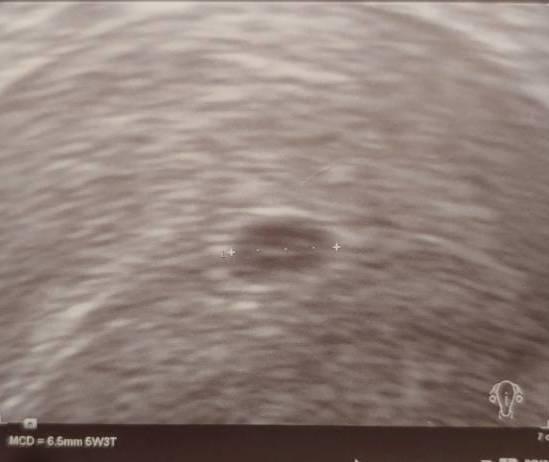

Ich hänge dir mal meinen Ultraschall von (sicheren) 5+3 an - da sieht man tatsächlich in den meisten Fällen noch nicht viel. Fruchthöhle und mit Glück die Anlage, wenn die nicht zu nah am Rand sitzt.

Bild zu